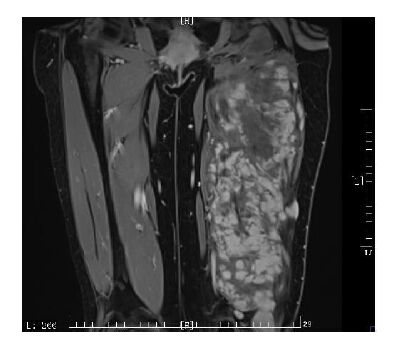

所有病例经MRI评估均无法在保留肢体功能及完整外观的情况下达到根治切除。我们在评估硬纤维瘤患者是否可以手术时,以硬纤维瘤是良性肿瘤为前提,谨慎权衡根治手术带给患者的获益和造成的损伤,按照安全切缘至少3 cm的标准,制定不可手术切除的标准为:根治手术会造成皮肤、肌肉等软组织的大块缺损,导致肢体外观的巨大改变及功能的丧失或需进行补片修补、皮瓣修复等重大重建手术;根治手术势必累及主要的血管、神经;肿瘤累及骨骼,在保留骨骼的前提下无法达到安全切缘;通过向患者交待病情,患者经过权衡利弊,拒绝尝试手术;截肢手术不予考虑。化疗方案具体为长春瑞滨(NVB)6~10 mg/m2 +小剂量甲氨喋呤(MTX)3~6 mg/(m2·d)5 次/周,预计化疗持续1 年。同时予以粒细胞刺激因子、保肝药等对症支持治疗。不可手术的硬纤维瘤示例见图 1,所示为一30岁女性患者,整个左大腿股后肌群均被肿瘤侵犯。

图 1 不可手术硬纤维瘤示例 Figure 1 Magnetic resonance image of inoperabledesmoid tumor in a representative case |